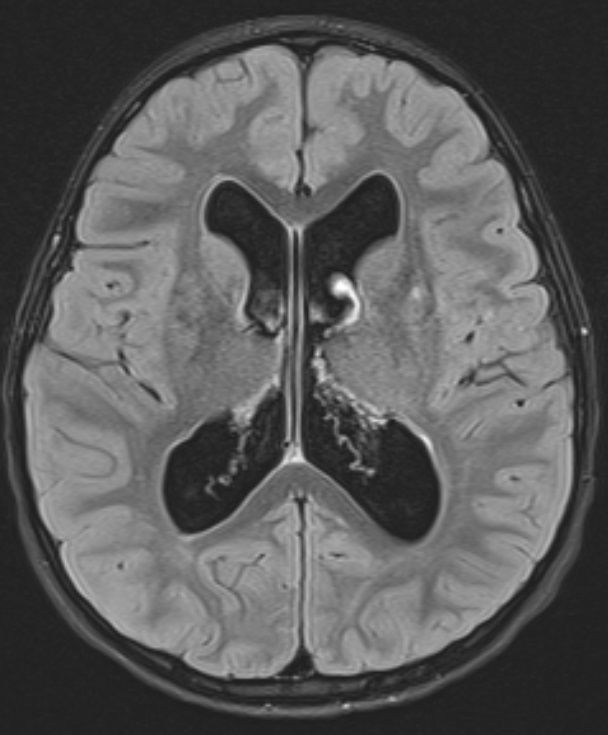

病例展示为1例6岁特发交通性脑积水患者,在计划和实施VP分流手术过程中涉及几点临床决策。

1例6岁男性患儿,有慢性头痛和语言迟缓症状,一次摔倒后撞伤头部遂行影像学检查。

脑室明显扩大。

轻度视乳头水肿伴头痛病史,经眼科检查确诊为脑积水。

交通性脑积水确诊理由:

四个脑室均扩大;

MRI对通过中脑导水管的CSF流动研究显示CSF流动通畅;

CISS/FIESTA 序列精细扫描研究未发现任何阻碍阻碍脑脊液流出的网状物。